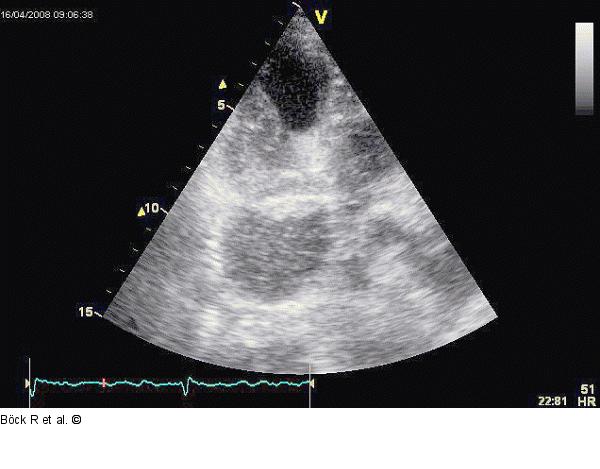

Abbildung 6: Sinus coronarius Kaudal angulierter Dreikammerblick mit Kontrastmittel im weiten Sinus coronarius zum rechten Ventrikel strömend. |

Kaudal angulierter Dreikammerblick mit Kontrastmittel im weiten Sinus coronarius zum rechten Ventrikel strömend. |